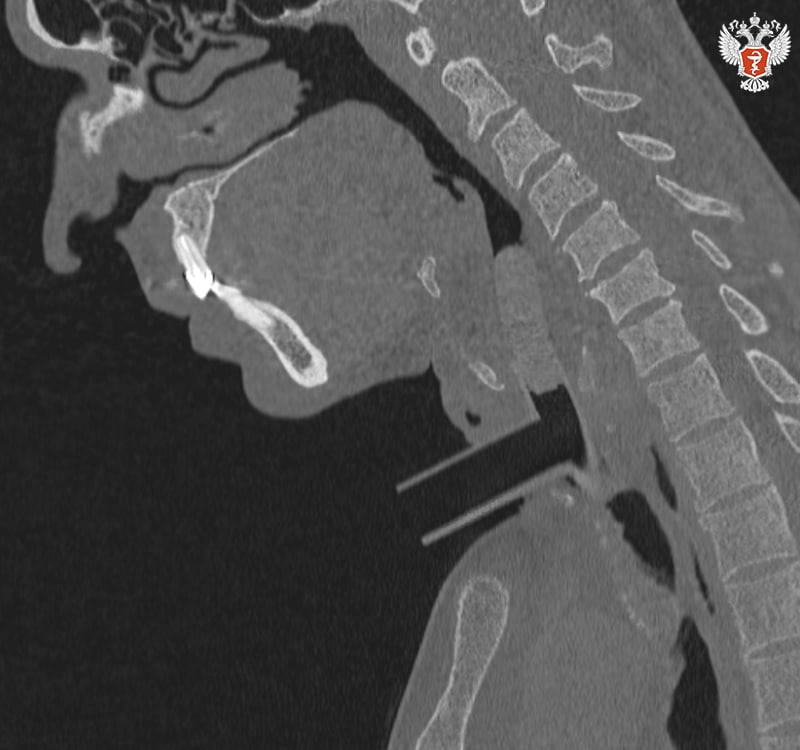

Специалисты Пироговского Университета Минздрава России и НИКИО им. Л.И. Свержевского представили новую систему анатомически адаптированных силиконовых стентов и комплексную тактику лечения хронического рубцового стеноза гортани и трахеи.

Хронический рубцовый стеноз гортани и трахеи — тяжелое заболевание, при котором возникает стойкое сужение просвета дыхательных путей вследствие разрастания плотной соединительной ткани, которое приводит к развитию дыхательной недостаточности.

анатомически адаптированные стенты точно повторяют контуры дыхательных путей, обеспечивая стабильный просвет и минимизируя травму;

комплексный алгоритм — от 3D-моделирования до контроля заживления — позволяет персонализировать лечение и предсказать результат;